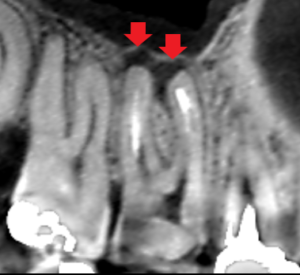

上顎第一大臼歯の口蓋根の矢状断のCT画像です。

矢印の先に膿の影がみられます。